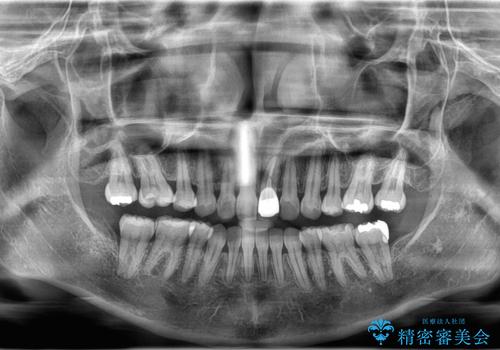

来院時、右下7遠心9mm、舌側6mmと深い歯周ポケットを認めました。

遠心から舌側、唇側に及ぶ深い垂直的骨欠損も認めたため、歯科衛生士による歯周基本治療の後、歯周外科(再生療法)を行いました。

レントゲン写真は、処置後一年経過時のもので、歯周ポケットは遠心4mm、舌側3mmまで減少、出血なし。

一度目の再生療法でできる骨形態は移行的でないこともあるため、経過を診つつ骨整形も必要であれば今後行う予定です。